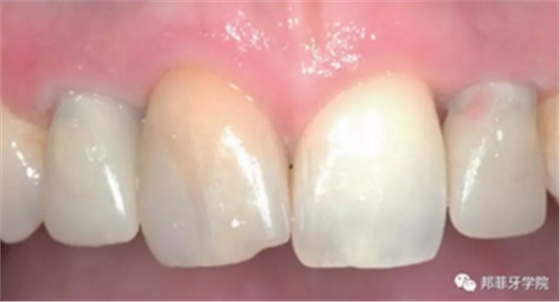

最終印模采用個性化印模柱,記錄穿齦輪廓(圖13)。CAD/CAM個性化基臺精確就位(圖14)。全瓷冠水門汀固位(圖15)。

圖 15-1:六個月后復查

圖 15-2:六個月后復查